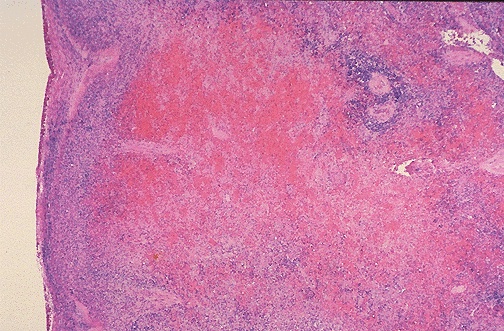

The section of spleen seen here at low power microscopically demonstrates a recent infarction.